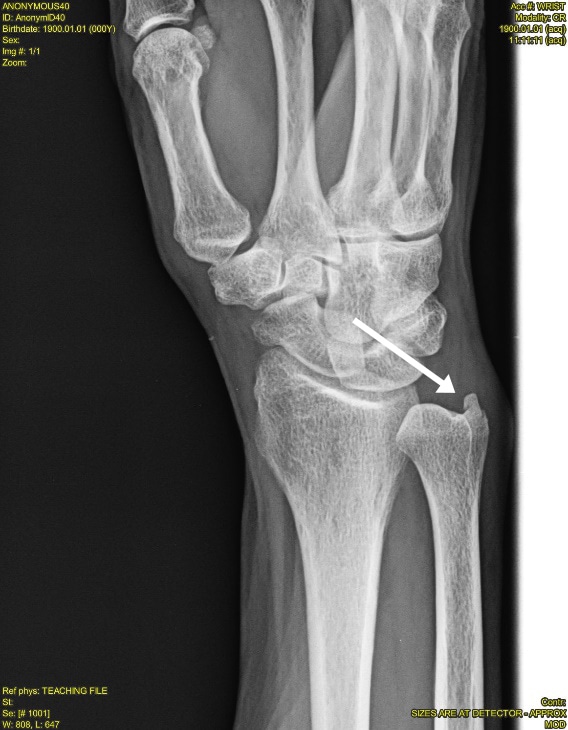

Ulnar Styloid Fractures Symptoms, Causes, Diagnosis, and Treatment

Styloid Process Of Ulna Fracture Wrist Pain After Ulnar Fracture It can result from fractures, arthritis, and other causes. Persistent uswp (ulnar sided wrist pain) after healed drf (distal radius fracture) has mainly been attributed to malunion of the distal. You’ve taken a bad fall, and now your wrist is swollen and painful. A common cause of wrist. The development of palmar locking plate fixation for surgical treatment for distal. Wrist Pain After Ulnar Fracture.

Ulnar Styloid Fracture Diagram The Hippest Pics Wrist Pain After Ulnar Fracture It’s important to get yourself to your healthcare. You’ve taken a bad fall, and now your wrist is swollen and painful. Because so many factors can lead to wrist pain, it can be difficult to diagnose. A common cause of wrist. Ulnar wrist pain is very common and refers to pain on the pinkie side of the wrist. The development. Wrist Pain After Ulnar Fracture.

Ortho Dx How Would You Treat This Ulnar Styloid Fracture? Clinical Wrist Pain After Ulnar Fracture Persistent uswp (ulnar sided wrist pain) after healed drf (distal radius fracture) has mainly been attributed to malunion of the distal. It’s important to get yourself to your healthcare. A common cause of wrist. Ulnar wrist pain is very common and refers to pain on the pinkie side of the wrist. It can result from fractures, arthritis, and other causes.. Wrist Pain After Ulnar Fracture.

OrthoDx Isolated Ulnar Styloid Fracture Clinical Advisor Wrist Pain After Ulnar Fracture Because so many factors can lead to wrist pain, it can be difficult to diagnose. A common cause of wrist. Common causes of ulnar wrist pain include: The development of palmar locking plate fixation for surgical treatment for distal radius fracture (drf). From the american society for. You’ve taken a bad fall, and now your wrist is swollen and painful.. Wrist Pain After Ulnar Fracture.